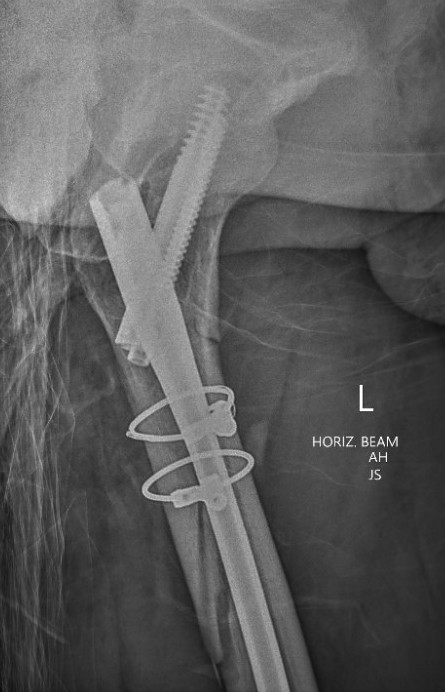

B. Cephalomedullary nails

- gold standard

- load sharing or load bearing, dependant on reduction

Piriformis reconstruction Gamma nail TFNA with helical screw Intertan nail

3. Varus malreduction associated with non union

- anatomical reduction key to union

- case series of 102 subtrochanteric fractures treated with IMN

- all nonunion occurred with varus > 10 degrees

- clamp assisted reduction of displaced subtrochanteric fractures

- all fractures within 5 degrees of anatomical in two planes

- 43/44 fracture united